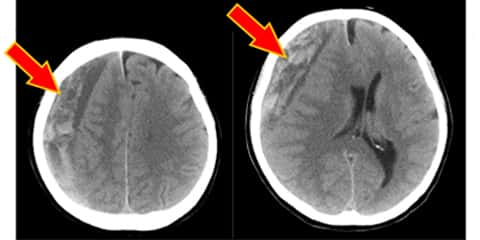

硬膜下血腫 確認すべき血液所見

慢性硬膜下血腫

外傷性硬膜下血腫の後遺症 症状は手術で治る 予後不良の後遺障害慰謝料はいくら アトム法律事務所弁護士法人